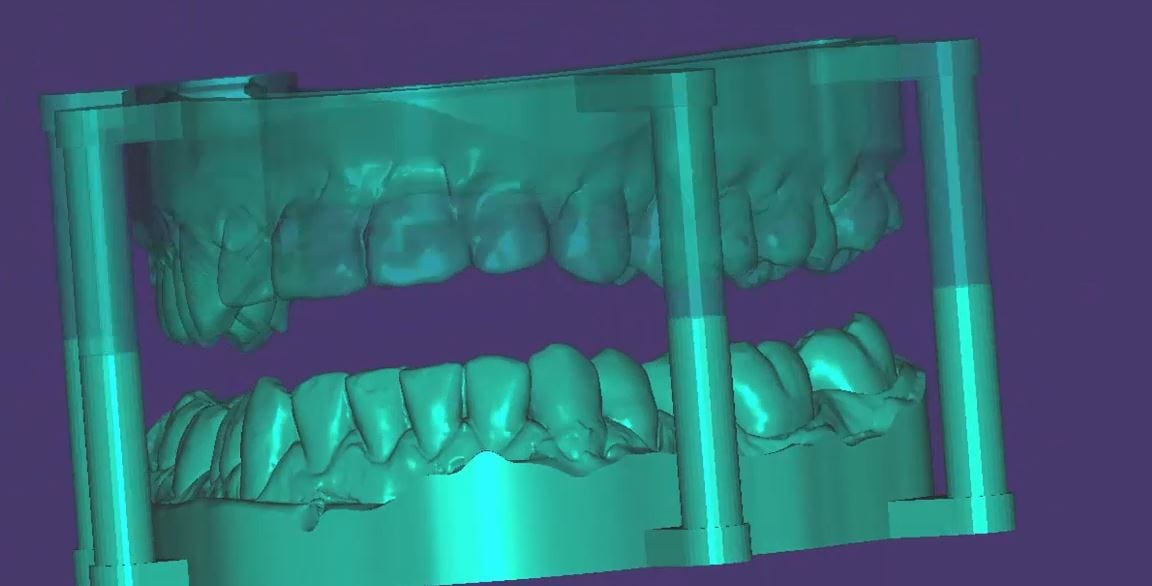

Support Pins for your Models for Oral Appliance Fabrication

May 29, 2019A friendly reminder- this case was table top scanned with a desktop scanner so don’t get distracted, but be aware that for oral appliances, particularly for apnea treatment or bruxism, […]